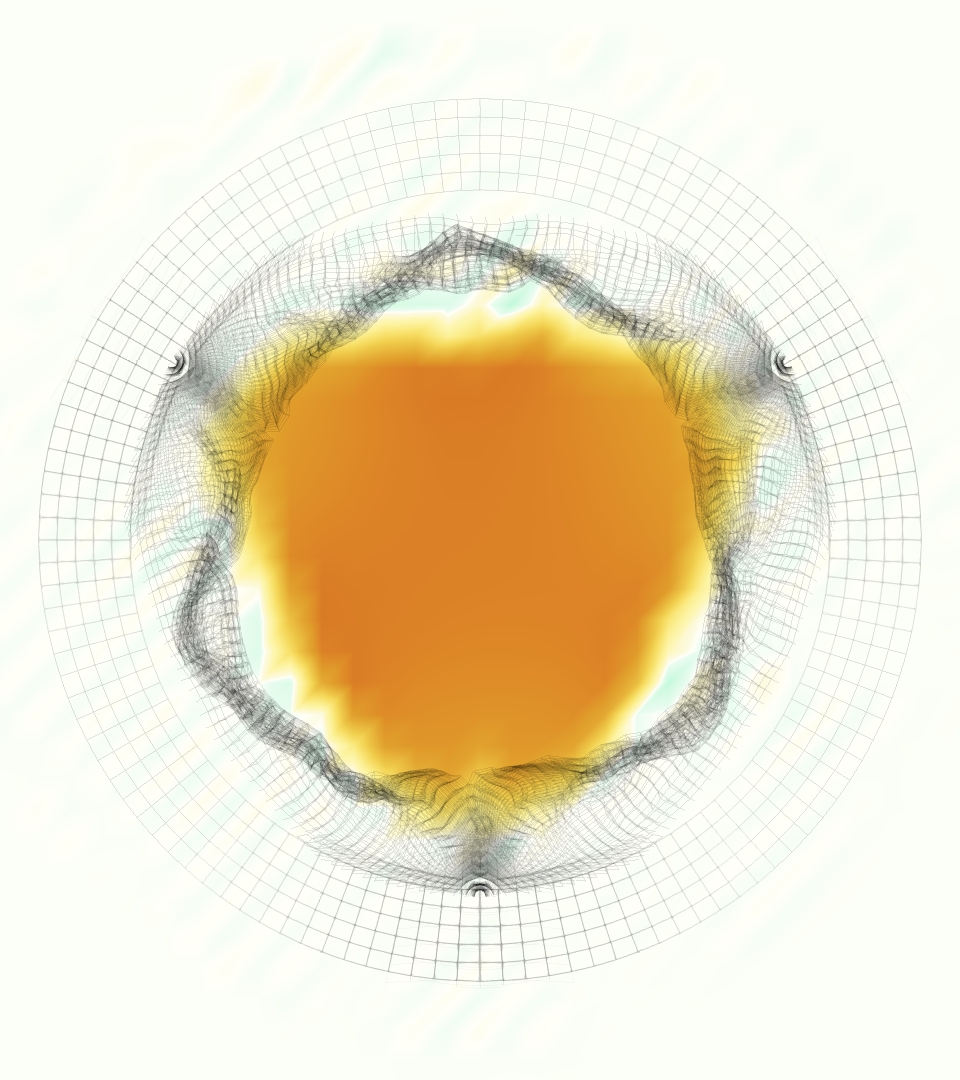

The phase-averaged, resampled velocity fields during peak systole and flow rates at each resolution are shown in Figure 10. Despite the limitations discussed above, we observe similar qualitative trends in the flow field at all resolutions. At all resolutions, a jet formed and angled up downstream of the valve orifice, as shown in the sagittal view. The jets showed a triangle-like cross section at with points aligned with the commissures. At cm, the jet appears like a rounded triangle in the opposing orientation, with its points aligned with the center of the leaflets. At cm, the jet is narrower downstream of the commissures, and wider downstream of the leaflets, again with a triangle-like cross section. The area of the jet increased with resolution, as expected given the IB method thickening of the valve structure. The narrowed jets at the two more coarse resolutions show locally elevated velocities relative to the two more fine resolutions. Figure 11 shows the instantaneous velocity fields at each resolution in the same axial and sagittal views. At 0.9 mm, the sagittal view shows a qualitatively different jet than at finer resolutions, with regions of lower velocity farther from the vessel wall, indicating insufficient resolution. At 0.9 and 0.68 mm, the jet is visibly narrowed compared to higher resolutions. While some features are similar at these two coarse resolutions, we conclude that the narrower jets indicate these simulations are under-resolved. Flows in the three finest resolutions, 0.45, 0.34 and 0.28 mm. appeared qualitatively similar, with slightly more fine structure detail in both the axial and sagittal views present at the edges of the jet. The jets in the axial views all showed a similar triangle-like cross section, slightly narrower downstream of the commissures, as in the phase-averaged fields. In both the phase-averaged and instantaneous fields, the three finest resolutions appear sufficiently similar that the conclusions of this study would be identical with any of these resolutions.

The flow rates, depicted in Figure 12, increase with increasing resolution, also as expected given the increase in effective valve orifice area and radius. The maximum flow rates at 0.45 and 0.34 mm were 248.6 and 281.4 ml/s, respectively, a relative difference of 11.7%. The mean flow rates at 0.45 and 0.34 were 55.5 and 63.2 ml/s, respectively, a relative difference of 12.4%. The maximum flow rates at 0.34 and 0.28 mm were 281.3 and 299.8 ml/s, respectively, a relative difference of 6.1%. The mean flow rates at 0.34 and 0.28 mm were 63.2 and 67.4 ml/s, respectively, a relative difference of 6.2%. Thus the flow rates show signs of converging with increasing resolution, though some minor differences remain.

Figure 13 shows the integral metric evaluated at cm with various resolutions, where each resolution uses its own velocity scale (see eqn. (18)). Values at 0.9, 0.68 were elevated relative to finer resolutions, indicating under resolution. Values of at 0.45, 0.34 and 0.28 mm are extremely similar, with slight decrease as resolution increases. Values of at 0.625 and 1.25 cm showed similar trends and are not shown.

Given the overall qualitative similarity and relative changes in flow rates, we believed all conclusions in this work would be similar with 0.45, 0.34 or 0.28 mm. We therefore selected 0.45 mm, twice the MRI resolution, for the main portion of this study.